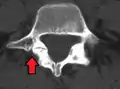

Anterolisthesis L5/S1

Isthmic anterolisthesis is where there is a defect in the pars interarticularis.[12] It is the most common form of spondylolisthesis; also called spondylolytic spondylolisthesis, it occurs with a reported prevalence of 5–7 percent in the US population. A slip or fracture of the intravertebral joint is usually acquired between the ages of 6 and 16 years, but remains unnoticed until adulthood. Roughly 90 percent of these isthmic slips are low-grade (less than 50 percent slip) and 10 percent are high-grade (greater than 50 percent slip).[9] It is divided into three subtypes:[13]

Computed Tomography (CT)

Computed tomography can be helpful in evaluating bony vertebral abnormalities, such as fractures.[33] This can be helpful in determining if the fracture is a new, old, and/or progressing fracture.[33] CT use in spondylolisthesis evaluation is controversial due to high radiation exposure.[34]